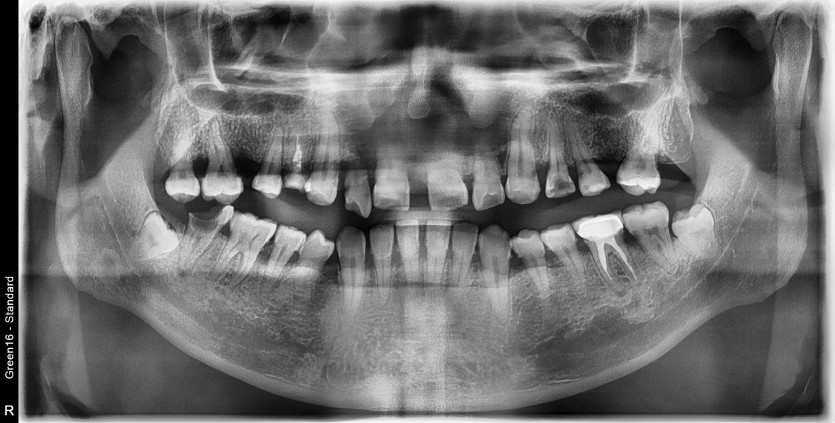

만 44세 상악 전체 임플란트 증례(하악 일부)

상악 전체 임플란트 증례입니다.(하악 일부)

13개의 임플란트로 완성하였습니다.